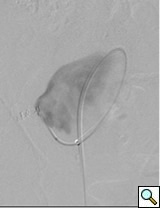

![]() |

| Figure 2: Various locations of iliac artery aneurysms and stent placements |

- Isolated iliac artery aneurysms are rare (Figure 2). Isolated internal iliac artery aneurysms are embolized. Pre-procedural embolization of internal iliac artery may also be necessary to prevents retrograde filling of the aneurysmal sac and late rupture. In case of aneurysm of distal part of external iliac artery contralateral access is gained and followed by a cross-over technique. This is done because the femoral access site will either be too close or may itself be part of the aneurysm. Same access applies for sub-intimal dissections and iliac occlusive disease in distal part of the external iliac artery. Majority of iliac aneurysms are accompanied with infra-renal aortic aneurysms that need to be treated concomitantly. Similarly, common iliac artery and proximal external iliac without proximal neck necessitates stent graft placement in the aortic bifurcation (Figure 3).